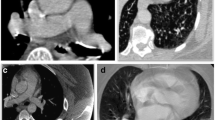

Various alterations to the traditional CTA PE protocol have been developed to overcome the differential streaming of contrast medium by focusing on the number of sites for contrast medium injection and the number of phases of acquisition [15, 16]. One technique utilizes dual sites of injection, one in an upper and one in a lower extremity vein, with a single acquisition. While another technique utilizes dual sites of injection and dual phases of acquisition. A third approach utilizes a single-site injection and single, late phase of acquisition. The fourth approach and one that is now favored by our team utilizes a single-site injection with dual phases of acquisition, also referred to as a biphasic CTA (Fig. 1). For biphasic CTAs, the initial acquisition typically evaluates the distal branch pulmonary arteries while the second acquisition evaluates the proximal Fontan circuit by allowing the contrast enough time for passive venous return. All four techniques have shown improvement over utilizing a single-site injection with single, early phase of acquisition. However, utilizing two IV sites to inject contrast is typically associated with double the discomfort with the added difficulty of obtaining venous access in a lower extremity that is of a sufficient caliber to allow for a power injection. Our study evaluated the use of a single-site injection with dual phases of acquisition compared to a single-site injection with a single, early phase of acquisition for optimal opacification of structures important for the evaluation of thromboembolic disease in the Fontan patient’s pulmonary circulation: SVC, IVC, Fontan, as well as the right and left branch pulmonary arteries.

There were three patients who had a biphasic CTA performed due to the diagnosis of thromboembolic disease on a prior monophasic CTA, one of which had been performed at an outside institution. Two of these three patients’ diagnoses were reversed based on follow-up biphasic CTAs. One of the two patients whose diagnosis was reversed presented to clinic with a 9-day history of chest pain and shortness of breath brought on by stress at work. An outpatient, monophasic CTA was obtained that was concerning for a Fontan thrombus due to suboptimal opacification of the central left pulmonary artery while there was good opacification of the distal left pulmonary artery (Fig. 1a, b). The other patient whose diagnosis was reversed had a history of chronic mycobacterium avium-intracellulare with associated chronic hemoptysis. This patient presented to an outside hospital with a more severe episode of hemoptysis. As part of the evaluation, a monophasic CTA was obtained that was reported to be concerning for “complete occlusion of the stent extending from the inferior vena cava to the pulmonary artery outflow tract.” The third patient was admitted to the hospital with plastic bronchitis awaiting heart transplantation while on room air. They developed poor perfusion with associated emesis and acute worsening of their ventricular function on echocardiogram that ultimately led to respiratory failure requiring intubation. On chest X-ray, there were findings consistent with pneumonia in the right lower lobe. However, there were persistent abnormalities on follow-up chest X-rays that could be attributed to a thromboembolic etiology as opposed to a right lower lobe pneumonia. Therefore, a monophasic CTA was obtained to evaluate for thromboembolic disease. On this CTA, there was concern for Fontan thrombus due to a filling defect in the distal right pulmonary artery and the branches to the right lower lobe. In addition to the filling defect, there was evidence of pulmonary infarction due to a triangular parenchymal opacity that abutted the pleural margin with internal air bronchograms peripheral to the branches of this right lower lobe pulmonary artery. This clinical presentation was felt to be consistent with Fontan thromboembolic disease and the patient was treated with anticoagulation. This patient’s follow-up biphasic CTA was performed one week after the initial monophasic CTA and its negative finding was attributed to anticoagulation treatment. There was one patient with Fontan circuit thrombus noted on a monophasic CTA, whose diagnosis was reversed based on follow-up cardiac MRI. This patient presented to the emergency department, while pregnant at 32 weeks of gestational age, with sharp sternal chest pain. The monophasic CTA that was obtained was unable to rule out thromboembolic disease due to streaming of contrast. Therefore, of the 5 positive monophasic CTAs, two were subsequently found to be falsely positive (Table 3).